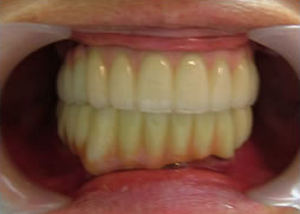

19.下は作った最終本物の歯が入りました。

これで治療終了。

開口器を入れた口元

治療完了

平成21年1月29日

(治療期間:1年7ヶ月)